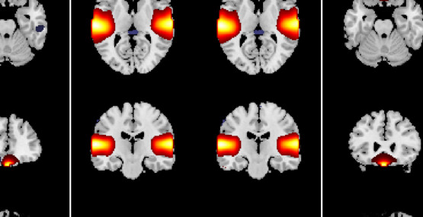

In the last two decades, unsupervised latent variable models---blind source separation (BSS) especially---have enjoyed a strong reputation for the interpretable features they produce. Seldom do these models combine the rich diversity of information available in multiple datasets. Multidatasets, on the other hand, yield joint solutions otherwise unavailable in isolation, with a potential for pivotal insights into complex systems. To take advantage of the complex multidimensional subspace structures that capture underlying modes of shared and unique variability across and within datasets, we present a direct, principled approach to multidataset combination. We design a new method called multidataset independent subspace analysis (MISA) that leverages joint information from multiple heterogeneous datasets in a flexible and synergistic fashion. Methodological innovations exploiting the Kotz distribution for subspace modeling in conjunction with a novel combinatorial optimization for evasion of local minima enable MISA to produce a robust generalization of independent component analysis (ICA), independent vector analysis (IVA), and independent subspace analysis (ISA) in a single unified model. We highlight the utility of MISA for multimodal information fusion, including sample-poor regimes and low signal-to-noise ratio scenarios, promoting novel applications in both unimodal and multimodal brain imaging data.